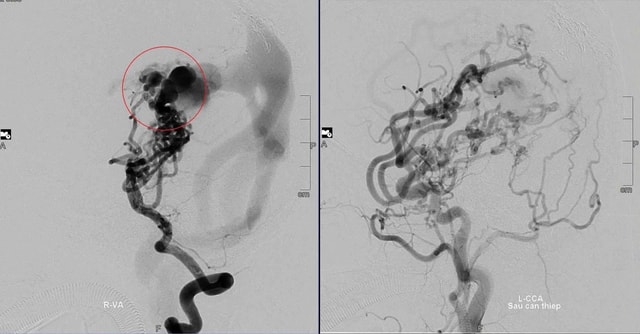

Ngay khi cất tiếng khóc đầu đời tại Bệnh viện Nhi Đà Nẵng, bé D. (ngụ ở Đà Nẵng, nay tròn 10 tuổi) đã tím tái, suy tim cấp, suy hô hấp nặng. Kết quả kiểm tra cho thấy trong não có khối dị dạng mạch máu bẩm sinh lớn, nhiều động mạch nuôi phức tạp và lưu lượng máu chảy qua rất cao.

Khi bé D. vừa tròn 1 tuổi, TS.BS Trần Chí Cường đã thực hiện ca can thiệp đầu tiên tại Đà Nẵng. "Đây là thử thách rất lớn. Khối dị dạng quá phức tạp, trong khi bệnh nhi lại còn quá nhỏ và dụng cụ can thiệp hạn chế" - chuyên gia chia sẻ.

May mắn, ca đầu tiên thành công ngoài mong đợi. Các bác sĩ hội chẩn và quyết định sẽ can thiệp nhiều giai đoạn để giảm lưu lượng máu, ngăn nguy cơ vỡ khối dị dạng.

"Suốt 10 năm, bé D. đã trải qua 8 lần can thiệp mạch não. Từ chỗ yếu liệt, khó khăn trong vận động và ngôn ngữ, bé D. đã có thể đứng và đi vững khi lên 3 tuổi rưỡi. Giờ đây, em học tập, vui chơi bình thường như bao bạn bè đồng trang lứa.